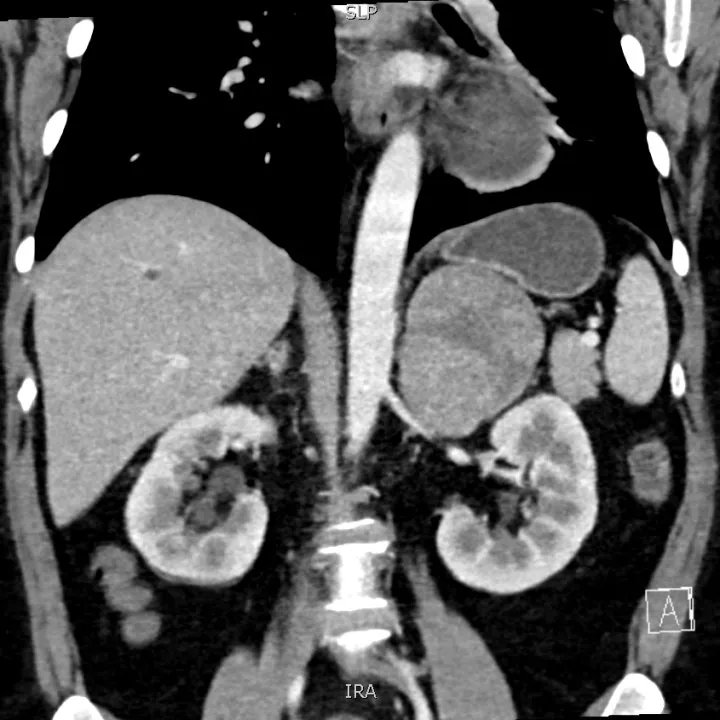

追问病史,患者坦言近一年体貌变化显著,体重明显增加,血压增高,且伴随持续性疲劳、阵发性多汗、心悸等症状。进一步的肾上腺功能检测显示,她的皮质醇、雄激素等关键指标显著异常。结合增强CT显示的肿瘤体积巨大、内部密度不均、强化不均匀等影像学特征,杨国胜诊断顾女士极可能是罕见的肾上腺皮质癌(Adrenocortical Carcinoma, ACC)。

▲肾上腺增强CT结果

如此巨大的肾上腺肿瘤绝非短期内形成,“患者多年未进行系统体检,直到肿瘤压迫器官引发水肿气促,以及激素紊乱导致典型外貌和严重高血压才被发现,这大大增加了治疗的复杂性和风险性。”杨国胜教授解释道,而且肾上腺皮质癌本身就容易侵犯周围组织,像这样巨大的肿瘤,很可能已经与肾脏、脾脏、胰腺甚至重要血管紧密粘连。